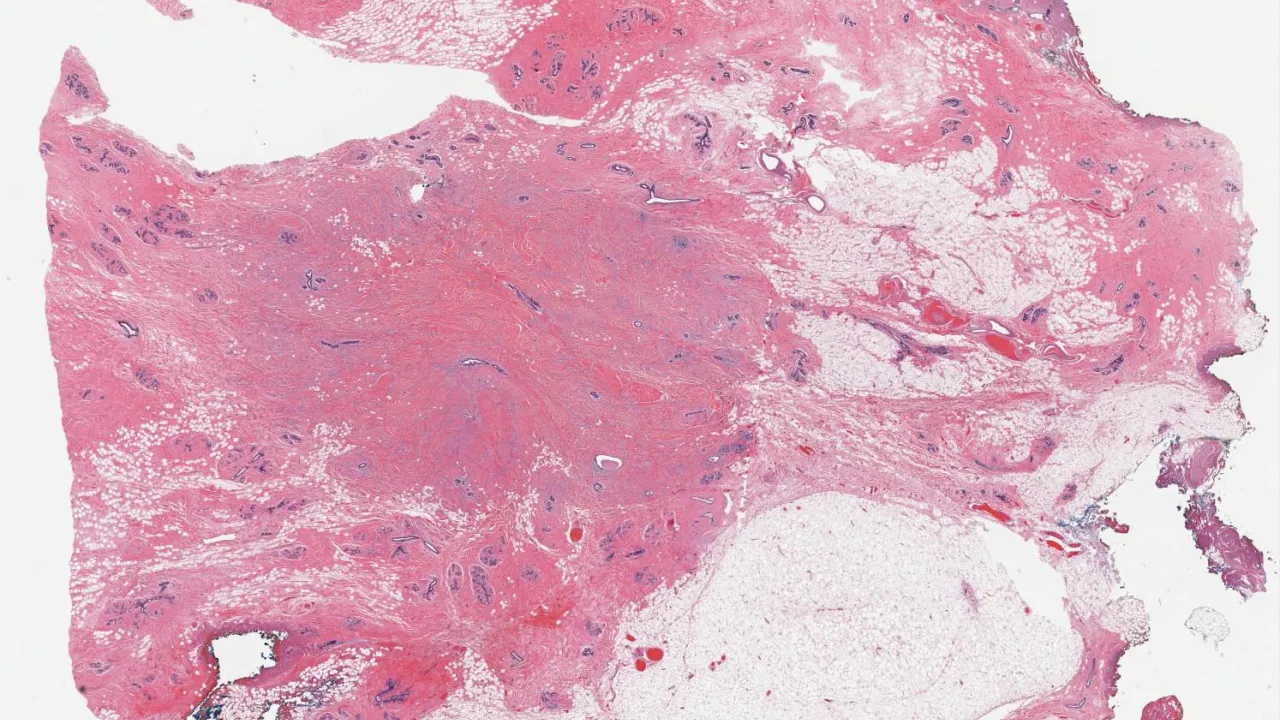

Breast, Epithelial-myoepithelial invasive carcinoma, S100 stain